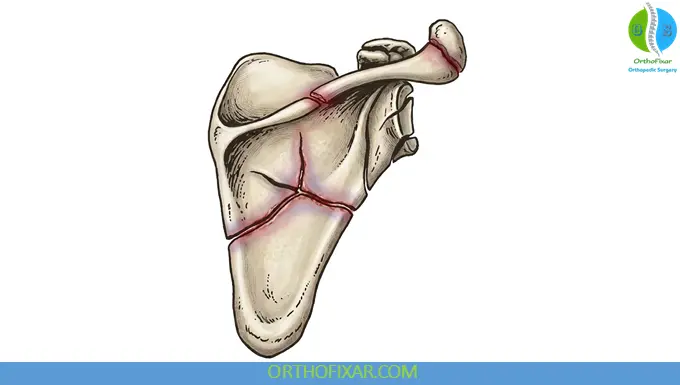

2. Ideberg Classification (Glenoid Fractures)

| Type Ia | Anterior rim fracture |

| Type Ib | Posterior rim fracture |

| Type II | Fracture line through glenoid fossa exiting scapula laterally |

| Type III | Fracture line through glenoid fossa exiting scapula superiorly |

| Type IV | Fracture line through glenoid fossa exiting scapula medially |

| Type Va | Combination of types II and IV |

| Type Vb | Combination of types III and IV |

| Type Vc | Combination of types II, III, and IV |

| Type VI | Severe comminution |